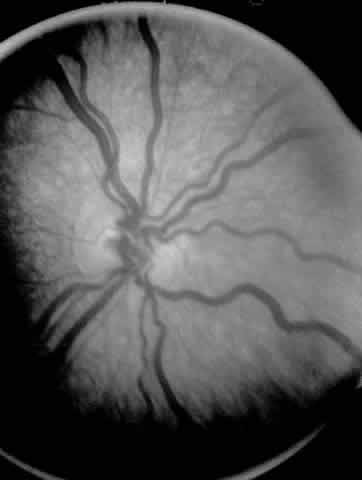

Fig. 3. Dilated and tortuous vessels in the posterior pole, which by definition is plus disease.